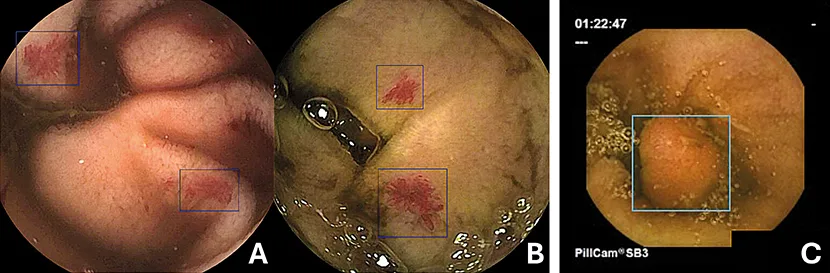

Figure 3 : Détection par IA en vidéo-capsule grêlique

A et B, angiodysplasie grêlique avec OMOM ; C, Polype de type harmatome du jéjunum avec assistance par AxaroLite, Augmented Endoscopy, Paris (Remerciement au Pr Xavier Dray).